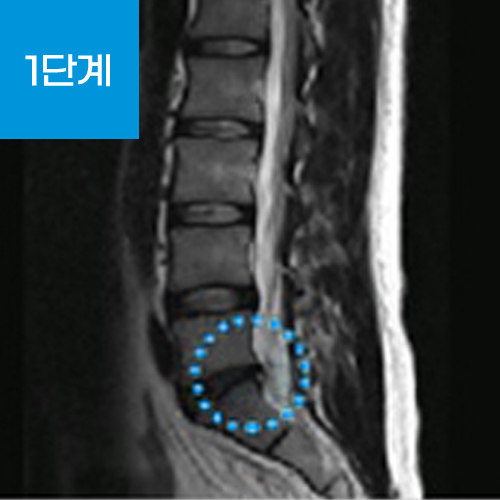

허리통증의 대표적인 질환인 허리디스크의 정확한 명칭은 추간판 탈출증입니다.

추간판(디스크) 중심에는 수핵과 수핵을 감싸는 섬유륜이라는 막으로 구성되어 있는데 추간판 탈출증이란 척추 뼈와 뼈 사이에서 완충 작용을 해주는 추간판(디스크)이 퇴행성 변화나 외상 등으로 추간판의 탄력이 저하되거나 손상되었을 때 수핵이 척추 바깥으로 탈출(튀어나옴)하게 되어 신경을 압박하여 통증을 느끼는 질환입니다.